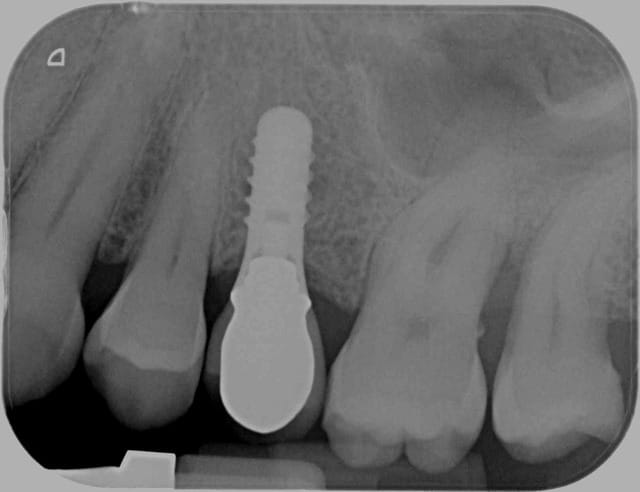

Dans le cas de ce patient j'ai coté HBQK443 car 4 secteurs en tout.

Montre les radios, ce sera plus simple.